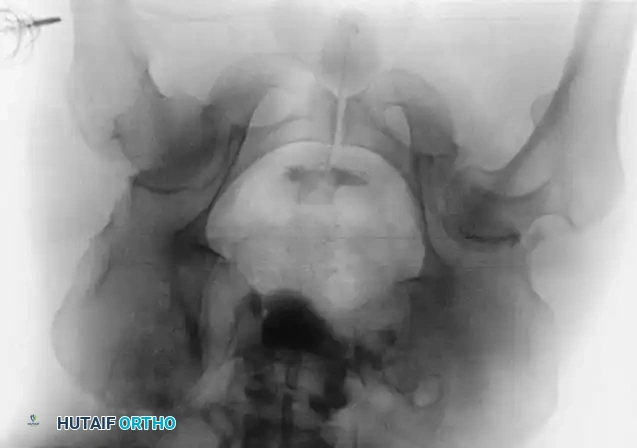

Associated Surgical & Radiographic Imaging

Hutaifortho's Orthopaedic Diagram